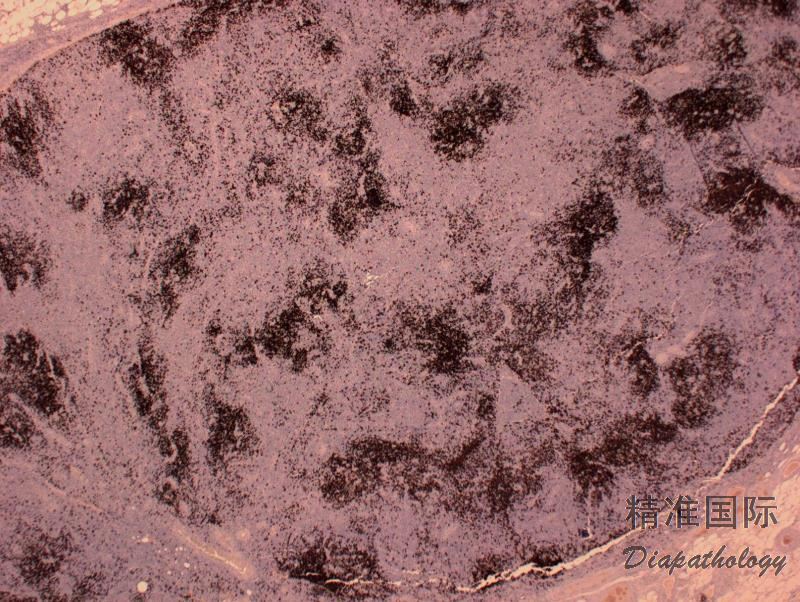

- 免疫表型:肿瘤细胞 CD3+、CD5+、βF1/TCR-αβ+、CD7+/-、CD4+,至少表达 2-3 个以上滤泡中心细胞抗原:Bcl6. CD10. PD1. CXCL13. ICOS、 SAP 和 CCR5,其中特异性较强的有 CXCL13 和 CD10,敏感性较高的有 PD1 和 ICOS。 CD21 和 CD23 显示滤泡树突细胞广泛增生,常围绕增生的高内皮静脉。有散在的 EBER+细胞(免疫母细胞样细胞,CD20+)。

免疫组织化学染色:

肿瘤细胞 CD3+、CD5+、βF1/TCR-αβ+、CD7+/-、CD4+,至少表达 2-3 个以下滤泡中心细胞抗原:Bcl6. CD10. PD1. CXCL13. ICOS、 SAP 和 CCR5,CD21 和 CD23 显示滤泡树突细胞广泛增生,常围绕增生的高内皮静脉。有散在的 EBER+细胞(免疫母细胞样细胞,CD20+)。